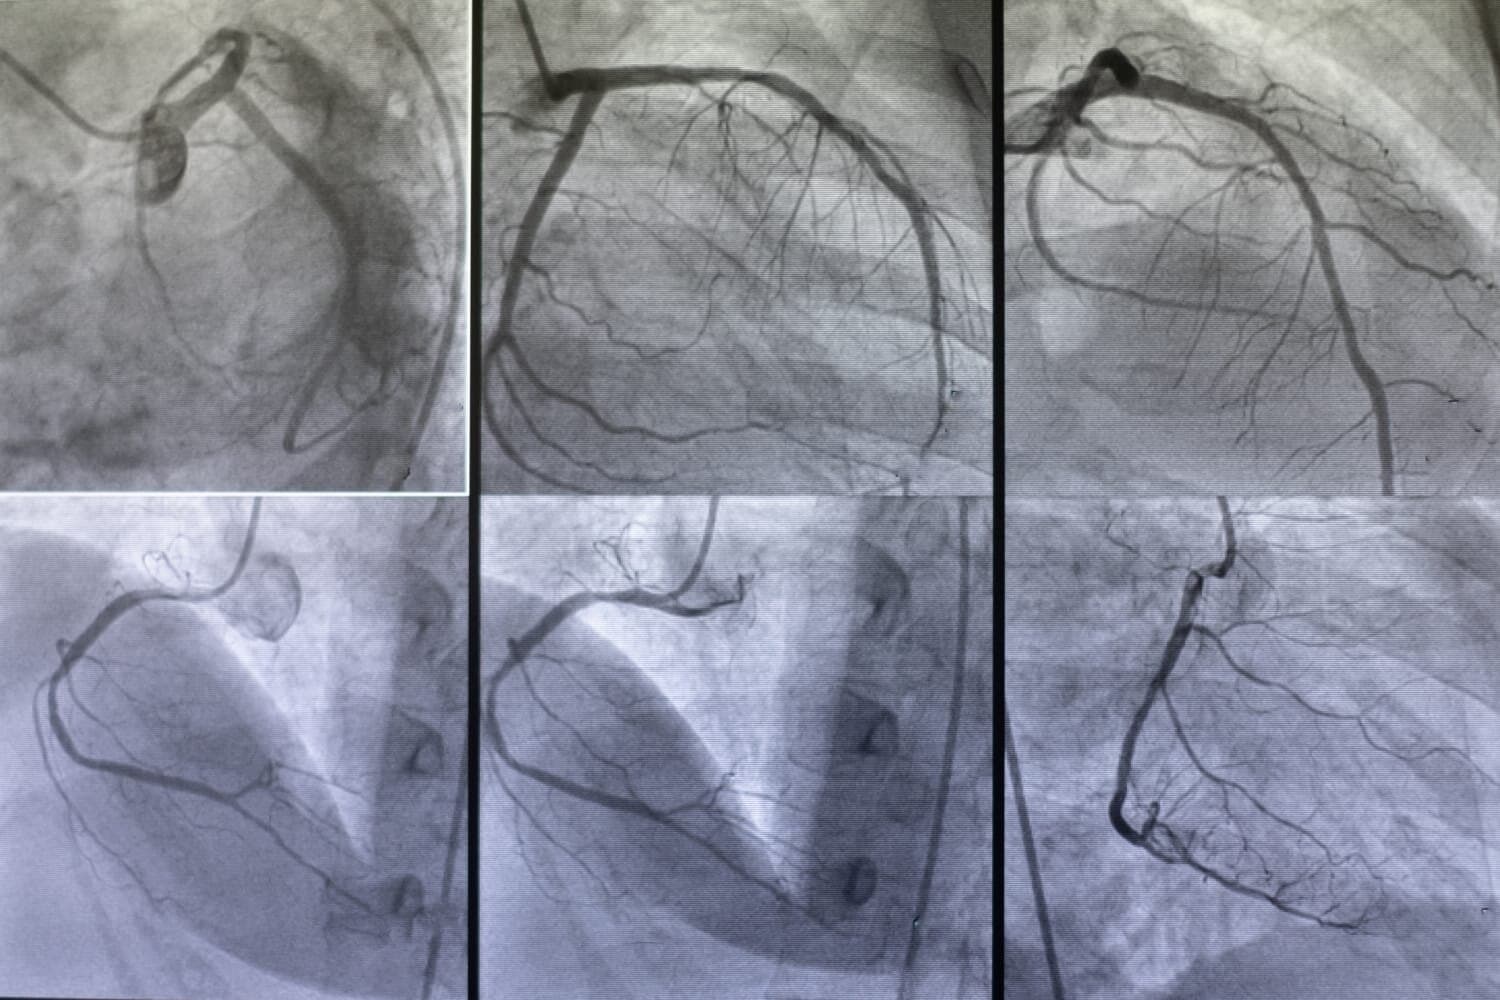

The process of angiography begins with the insertion of a catheter, a thin flexible tube, into a blood vessel. This is usually done through an access point in the groin or arm. The catheter is then carefully guided to the area of interest under the guidance of fluoroscopy, a type of real-time X-ray imaging. Once in position, the contrast dye is injected through the catheter, and a series of X-ray images are taken to capture the enhanced view of the blood vessels.

Once the area is numb, a small incision is made, and a thin, flexible tube called a catheter is inserted into the blood vessel. The catheter is carefully guided through the vascular system to the area of interest using real-time X-ray imaging, known as fluoroscopy. This allows the physician to navigate the catheter precisely to the target location.

After the catheter is in place, a contrast dye is injected through it into the bloodstream. This dye makes the blood vessels more visible on X-ray images, providing a clear view of any blockages, narrowing, or other abnormalities. Multiple X-ray images are taken in rapid succession as the dye moves through the blood vessels, allowing the physician to observe the flow of blood and identify any issues.

The angiography procedure begins with the patient lying on an X-ray table in a specialized angiography suite. The area where the catheter will be inserted, usually the groin or arm, is thoroughly cleaned and numbed with a local anesthetic to ensure patient comfort. Once the area is numb, a small incision is made, and a thin, flexible tube called a catheter is inserted into the blood vessel. The catheter is then carefully guided through the vascular system to the area of interest under the guidance of real-time X-ray imaging, known as fluoroscopy. This allows the physician to navigate the catheter precisely to the target location.

Once the catheter is in place, a contrast dye is injected through it into the bloodstream. The contrast dye enhances the visibility of the blood vessels on X-ray images, providing a clear and detailed view of any blockages, narrowing, or structural abnormalities. Multiple X-ray images are taken in rapid succession as the dye moves through the blood vessels, allowing the physician to observe the flow of blood and identify any issues.